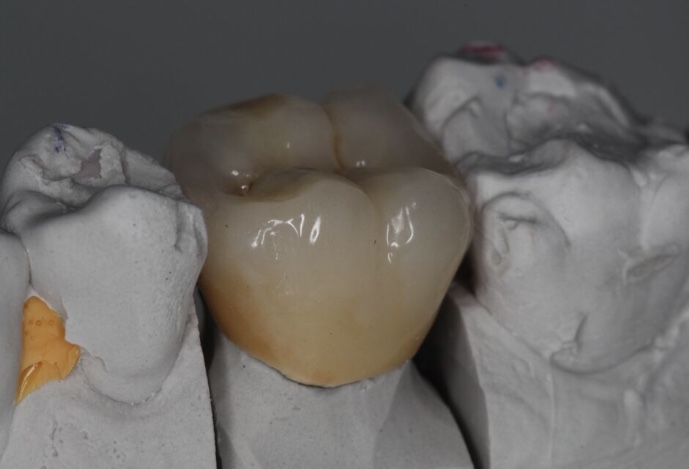

E-Max

L’E.max®, 100% céramique, est à base de disilicate de lithium, reconnu pour sa haute résistance à la flexion (500 Mpa).

Elle est donc une alternative esthétique aux restaurations céramo-métalliques, conservant, ensemble, éclat et durabilité.

Couronne, bridge de 3 éléments, inlay, onlay, facette